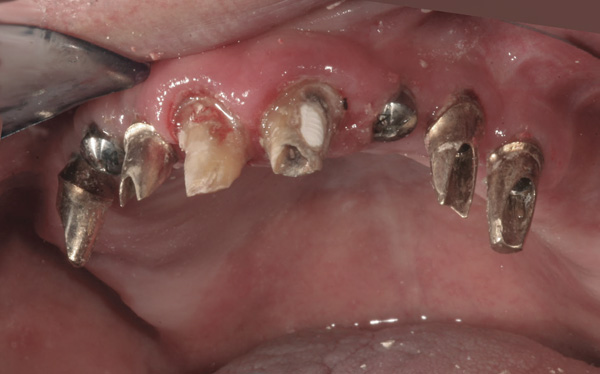

Background: In this case, the patient had a failing mandibular and maxillary dentition due to caries secondary to radiation-induced xerostomia. The patient had had a radical neck dissection to remove a squamous cell carcinoma of the throat 9 years prior to his prosthodontic consultation with the authors. The patient reported a history of radiation therapy following surgery, but did not have a shielding stent. A staged approach was used so as to avoid removable prosthetics on his severely dry soft tissues. He chose to treat his mandibular issues first. Figure 9 shows healing abutments next to the temporarily retained natural teeth, and Figure 10 shows the first-stage custom abutments inserted with relatively good gingival contour and no recession. Recession was clearly seen around all first-stage abutments following adjacent extractions and second-stage implant placement (Figure 11).

Figure 9 Healing abutments.

Figure 9

Figure 10 First-stage custom abutments.

Figure 10

Figure 11 Recession evident around first-stage abutments following adjacent extractions and second-stage implant placement.

Figure 11